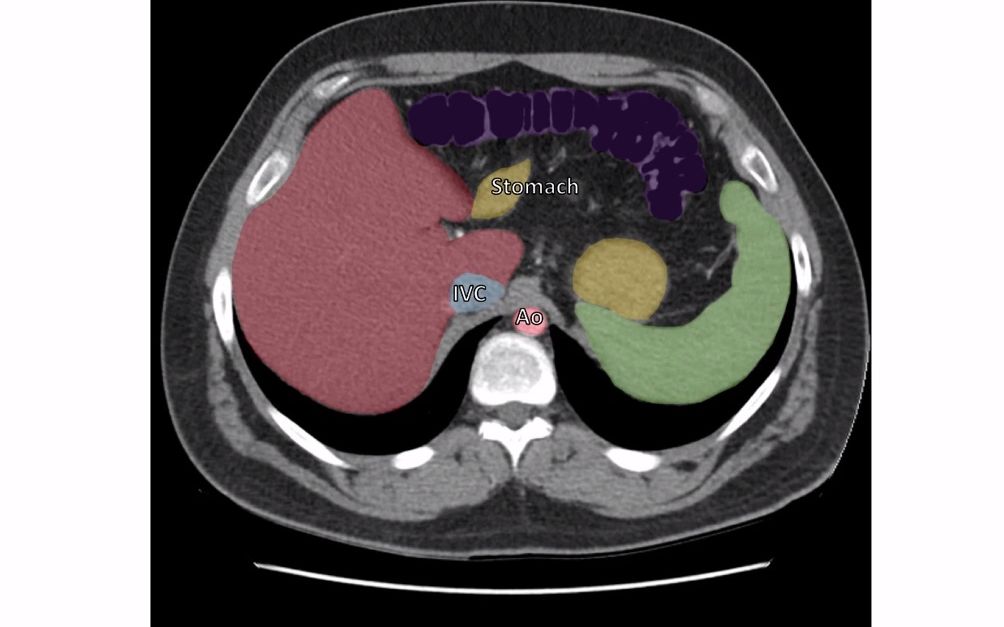

胸腔(the thorax)的横截面ct解剖

彩色图谱教你看胸部ct横断面